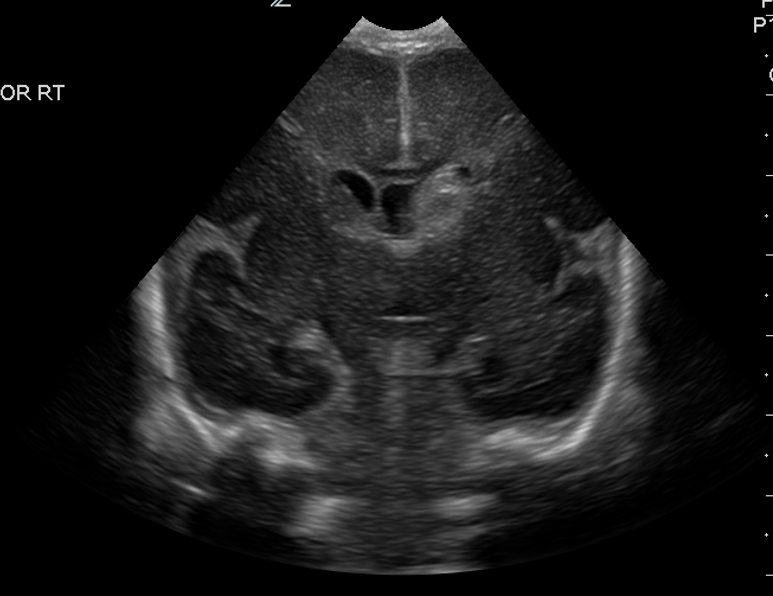

Info Images Findings Impression Reco/Acuity Case Images View Images / Launch Visage Case Notes History Full term infant. We are asked to evaluate posterior fossa cyst. Exam Gray scale and Doppler Ultrasonographic examination of the head. Prior Study N/A Dicom View Reference Material

Section 1 Submit Findings Case149 Findings Brain The brain is immature. Yes No There is under-sulcation and open sylvian fissures. Yes No There is/are multiple hypoechoic areas in the periventricular white matter. Yes No There is/are multiple hyperechoic areas in the periventricular white matter. Yes No There is diffuse cerebral edema with diffusely increased echogenicity of the brain parenchyma and loss of grey white matter differentiation. Yes No The thalami/basal ganglia are hypoechoic. Yes No There is periventricular calcification. Yes No There is intra-parenchymal calcification. Yes No CSF spaces/ventricular system There is a prominence of the extra axial fluid spaces. Yes No There are debris/septations in the extra axial fluid spaces. Yes No There are debris/septations in the ventricles. Yes No There is a subdural collection on the right/left side. Yes No There is prominence of the ventricular system. Yes No There is an asymmetry of the ventricular system. Yes No There is a cavum septum pellucidum. Yes No There is a midline shift towards right/left. Yes No The choroid plexus is bulky/lobulated. Yes No There is a choroid plexus cyst measuring… Yes No There are debris/clots in the occipital horn. Yes No There is a posterior fossa cyst measuring… Yes No The tentorium is elevated/depressed. Yes No The lateral ventricle/s are dilated. Yes No The third ventricle is dilated. Yes No The 4th ventricle is dilated. Yes No There are pseudo cysts. Yes No Germinal matrix hemorrhage (Only in the premature infants): Please do not answer if the patient is a full term. There is a germinal matrix hemorrhage, consistent with a grade I hemorrhage. Yes No There is an intraventricular extension consistent with a grade II hemorrhage. Yes No There is an intraventricular extension with the dilatation of ventricles, consistent with a grade III hemorrhage. Yes No There is an intra-parenchymal extension, consistent with grade IV hemorrhage. Yes No On color Doppler examination, the Resistive index in the anterior cerebral artery is… There is a loss of the diastolic flow on the Doppler exam. Yes No There is altered vascularity on Doppler imaging. Yes No There is an AVM in the region of… Yes No